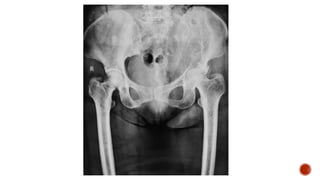

 AP and lateral radiographs of the skull show multiple tiny lucent areas with areas of

sclerosis in between, giving rise to salt and pepper skull appearance.

 Radiographs of both the legs, knees and left humerus show diffuse osteoporosis with

few well defined lytic areas.

FINDINGS

 Osteopenia

 Subperiosteal resorption: classically along radial aspects of phalanges

 Floating tooth

 Subchondral resorption (lateral end of clavicles, pubic symphysis, sacroiliac joints)

 Subligamentous resorption(ischial tuberosity, trochanters)

 Brown tumors(more common in primary)

 Salt and pepper skull

 Rugger jersey spine